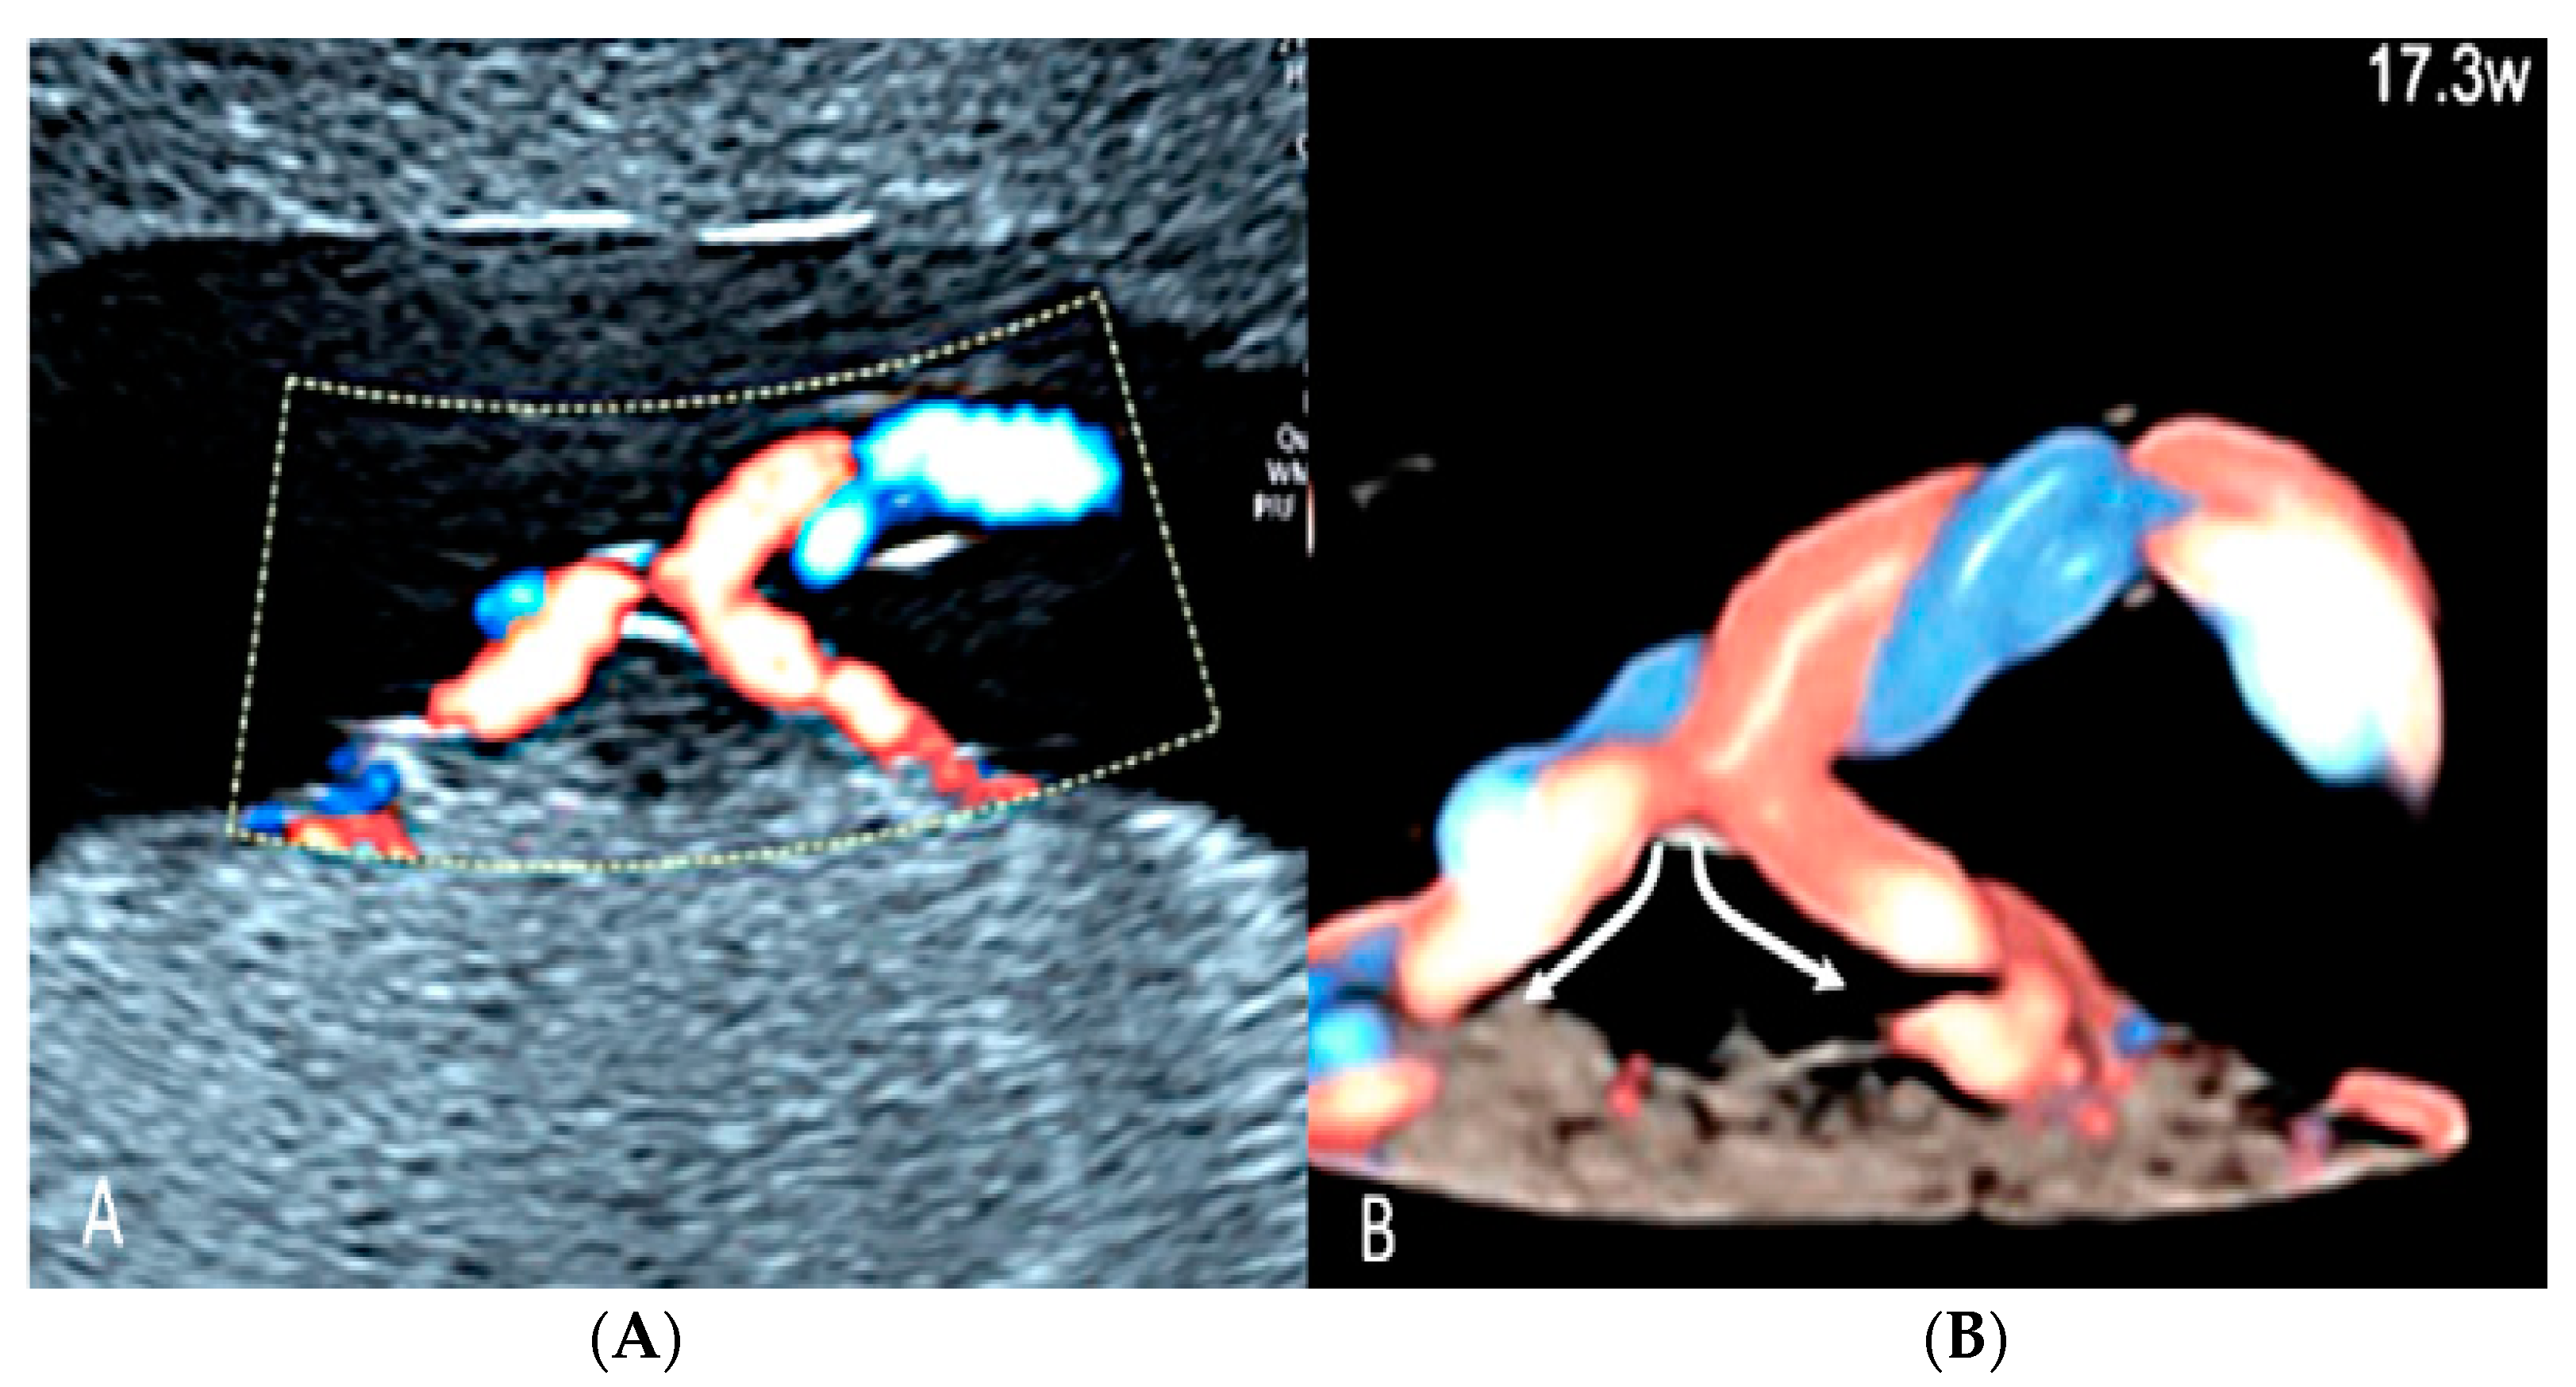

3.2.5. Furcate Umbilical Cord Insertion

Furcate umbilical cord insertion is a condition where the umbilical vessels separate before they insert into the placental plate and lose their Wharton’s jelly [59,60]. It is present in 0.1% of pregnancies and is considered a variant not well distinguished from velamentous cord insertion [59,60] (Figure 24).

Figure 24.

Furcate umbilical cord insertion using two-dimensional ultrasound (A) and three-dimensional ultrasound (B) with HD-Flow™ Doppler: the dichotomic direction of the umbilical blood flow is clearly demonstrated at 17.3 week’s gestation (arrows).